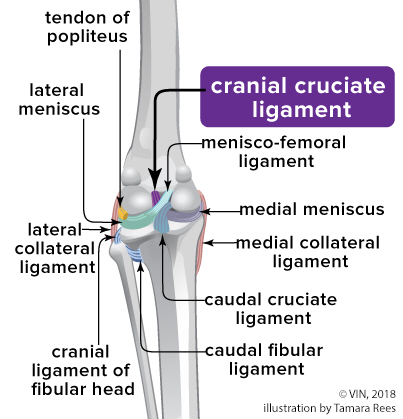

The knee joint or stifle connects the thigh to the lower leg. Inside the knee are cartilage plates (meniscus) and ligaments (cruciate ligaments). In dogs and cats, these ligaments are called cranial (CCL) and caudal (CaCL).